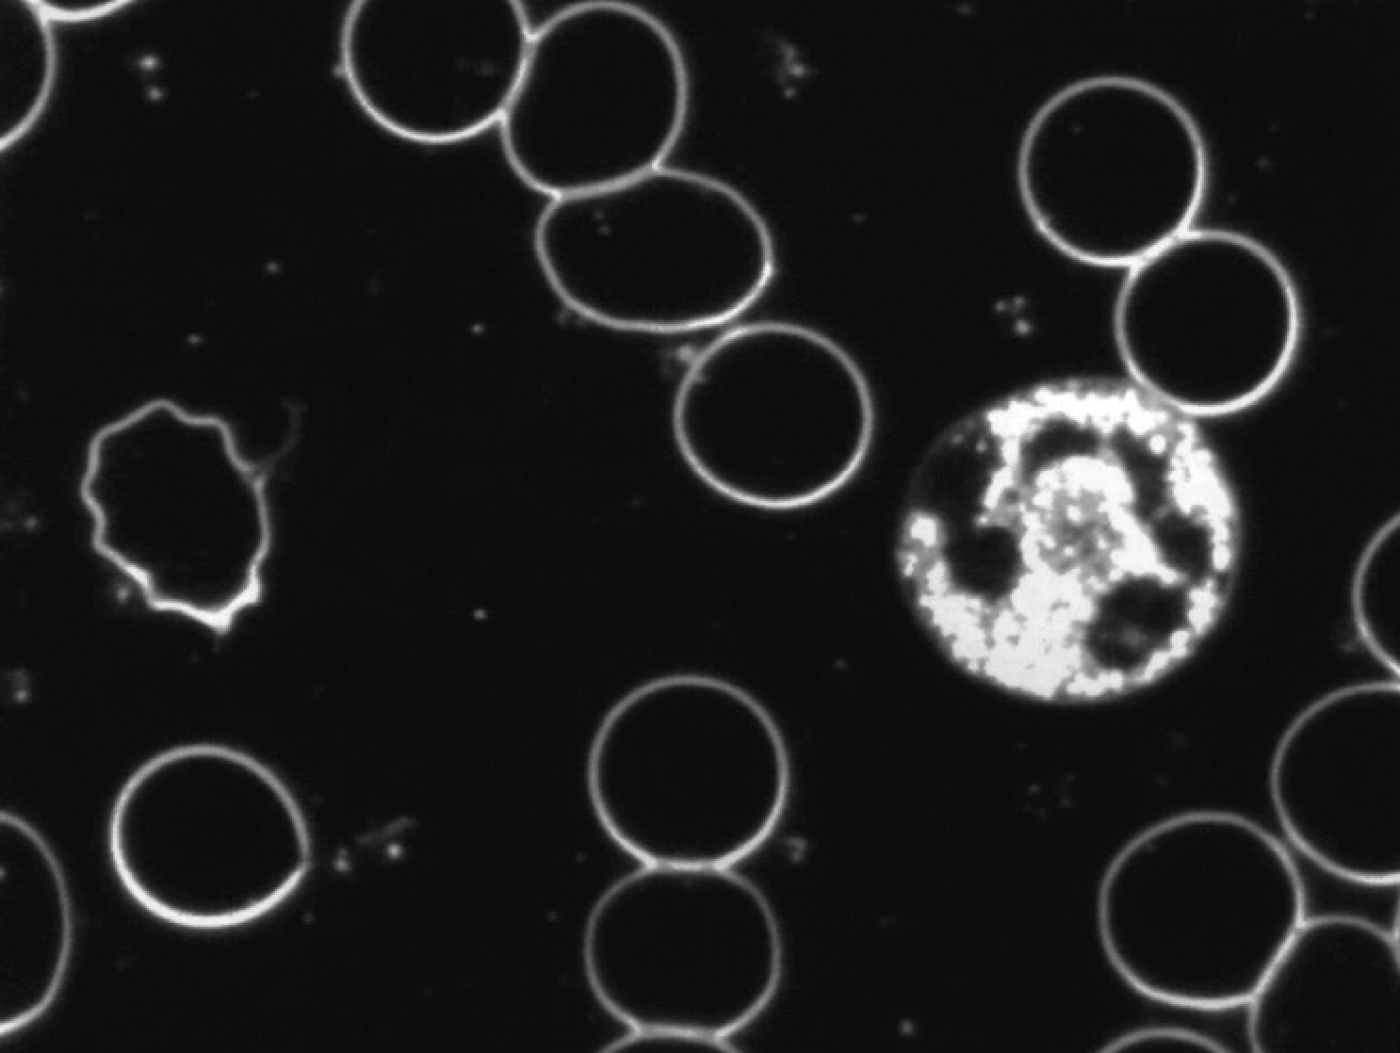

Levend bloedbeeld

na neutralisatie met Benzoliet

De veranderingen die werden geconstateerd na neutralisatie van de toegepaste verstorende subtiele energieën door Benzoliet in met name de witte cellen waren:

- toegenomen mobiliteit

- toegenomen en homogeen over de cel verspreide cytoplasmatische activiteit

- verlaten van de bolvorm

- het vormen van pseudopodieën

Hieruit volgt de conclusie dat Benzoliet in staat is de in de proef toegepaste verstorende subtiele energieën te neutraliseren en dat door neutralisatie het afweersysteem beter kan functioneren.